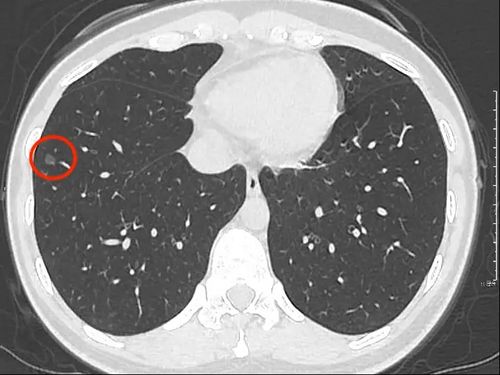

混合磨玻璃结节有明显的血管进入观察半年无消散要考虑手术

病例(14例)阐述肺部结节的ct诊断策略

磨玻璃结节图片